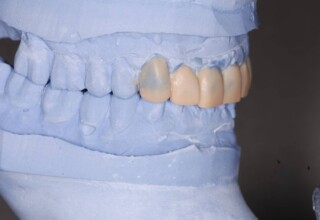

Porcelain Veneers

The best way to solve esthetic problems of the anterior teeth. They combine very little tooth grinding with very high esthetic performance. In the following extensive case anterior teeth presented with: old restorations, staining, poor shape, length and tooth –gingiva ratio. Meticulous diagnostic waxing was performed on study casts and temporary veneers were manufactured. Temporary veneers were used intraorally to evaluate the incorporated changes and to further modify and adjust were needed. When esthetics and function were approved by the patient and were satisfying for the operator the temporaries were used as a guide for the final porcelain veneers. The five final veneers on the upper anterior teeth restored the smile of the patient to almost perfection.

Initial appearance

Final appearance